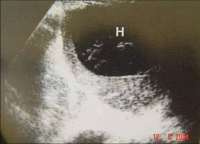

②B型超声检查:

Bk8b4.jpg

脾被摸下破裂

脾真性破裂

B超(左起图1脾中央破裂图2脾被摸下破裂图3脾真性破裂右图胃肠破裂穿孔)检查具有经济方便、可在床边检查、可重复进行动态观察、无创无痛、以及诊断准确率高等优点,因此其在腹部损伤的诊断中倍受重视.应用越来越广泛。 对肝、脾、肾等实质性脏器损伤,B超检查的确诊率达90%左右。可发现直径1— 2cm的实质

血肿,并可发现脏器包膜连续性中断和实质破裂等情况。超声检查对腹腔积液发现率很高。并可根据B超检查估计出腹腔积液的量,即每lcm液平段,腹腔积液约有500ml。由于气体对超声的反射强烈,其在声像图上表现为亮区。因此,B超检查也可发现腹腔内的积气,有助于空腔脏器破裂或穿孔的诊断。

急性胃穿孔。左叶肝前方见气体强回声